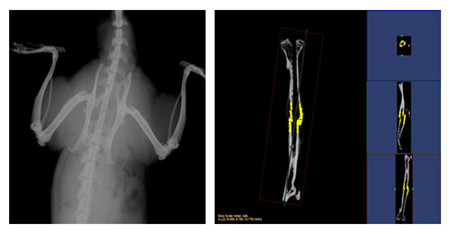

小動物CT服務通過采用錐形X線束,不僅能夠獲得真正各向同性的容積圖像,提高空間分辨率,提高射線利用率,而且在采集相同3D圖像時速度遠遠快于扇形束CT。可以對不脫鈣骨骼和動物牙齒進行microCT檢測服務,分析其內部結構和提供給您高清晰、高質量的掃描圖像。活體研究對象通常為小鼠、大鼠或兔等活體小動物,可以實現生理代謝功能的縱向研究,顯著減少動物試驗所需的動物數量;離體研究對象通常為離體標本(例如骨骼、牙齒)或各種材質的樣品,可分析其內部結構和力學特性。

結果示意圖:

小動物CT結果示意圖

小動物CT結果示意圖小動物CT結果示意圖